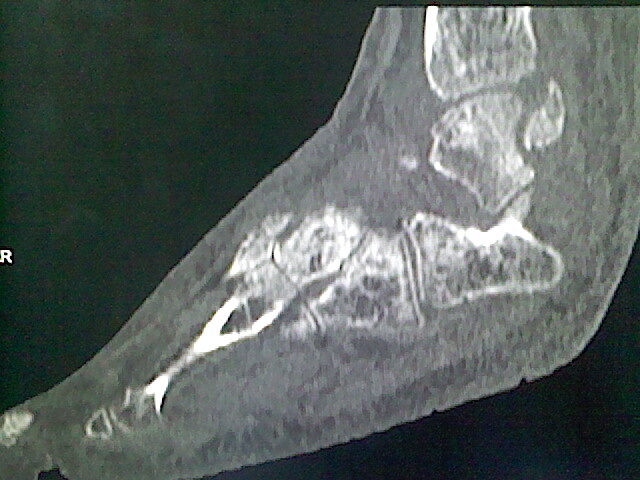

标题: CT16814:男,76岁,左小腿疼痛,不能站立 大家给看看 [打印本页]

男,76岁,左小腿疼痛,不能站立

本例骨质改变主要表现为滑膜或韧带区的骨侵蚀融解(胫腓联合区骨质破坏无硬化边),距骨后部骨质破坏区有硬化边及死骨样改变.所以,本例考虑关节结核可能性大,绒毛膜结节性滑膜炎多发于中年,且极少见于膝髋以外的关节,骨质硬坏也以压陷吸收为主,有明显的硬化边,骨膜增生呈结节状(可以mr鉴别),所以本例暂除外.

另不除外可引起相似表现的其他炎症如布氏杆菌性关节炎等